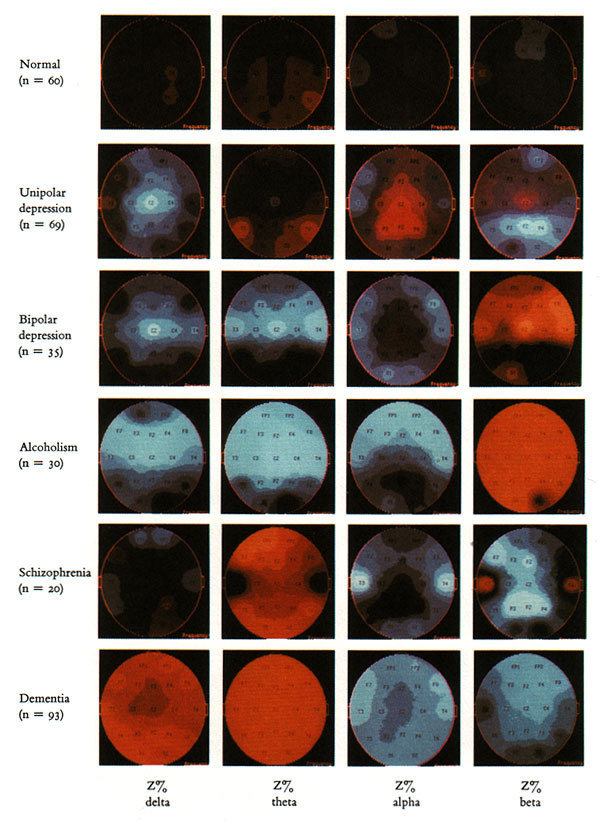

Двумерная индексация изображений немного усложняет процесс восприятия, но при этом существенно обогащает графическое высказывание в целом. Вот, например, нейрометрические карты электрической активности мозга собраны с матрицу: строки — индивидуальные диагнозы, столбцы — частотные полосы (дельта, тэта, альфа и бета).

Графически этот пример напоминает диаграмму смогов из первой главы.

В примере с нейрометрическими картами все картинки имеют черный фон, и эти фоны создают ненужные, мещающие восприятию белые пересечения. Однако, соотнести изображения между собой можно и более элегантным, менее визуально агрессивным способом, как, например, на картинке с насекомыми: каждой букашке легко подобрать пару имитирующей её наживки. Да и более сдержанная цветовая гамма здесь работает лучше, чем буйство красок из предыдущего примера.